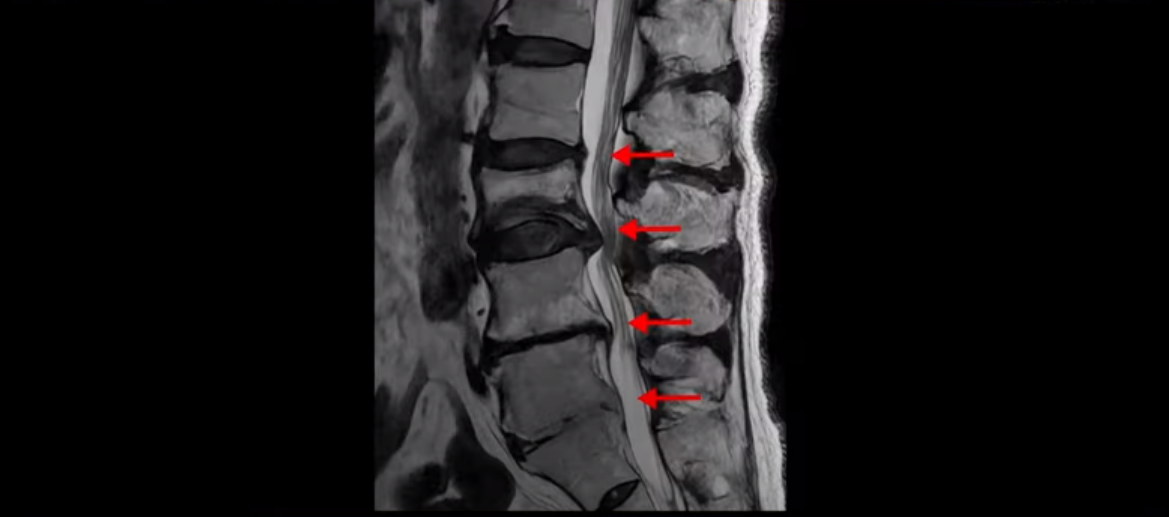

MRI를 보면 허리 4마디가 심하게 퇴행되어 있고

3번 뼈는 넘어질 때 생긴 압박골절이 있습니다.

3번 4번에는 척추관협착과 디스크 탈출이 보이고

4번 5번에는 척추관협착과 심한 디스크 파열이 있습니다.

5번 1번에는 뼈가 자라난 골극이 있고

기립근의 지방화도 심합니다. 또 3번 4번 마디에서는 신경가지가 빠져나가는 추간공이 왼쪽, 오른쪽 모두 많이 좁아져 있습니다.